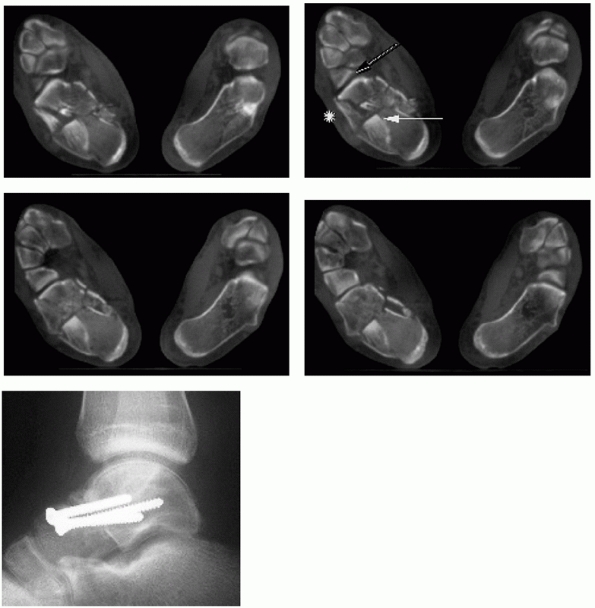

![]() |

FIGURE 59-27

Percutaneous fixation for Sanders 2B split tongue-type fracture. The patient also sustained a contralateral proximal humerus fracture and a spinal cord contusion and developed a pulmonary embolus requiring anticoagulation, necessitating percutaneous reduction and fixation. A. Lateral radiograph demonstrating restoration of calcaneal height and crucial angle of Gissane. B. Broden view demonstrating anatomic reduction of posterior facet (black arrow). C. Axial view showing residual shortening and varus malalignment of tuberosity (black arrow). |